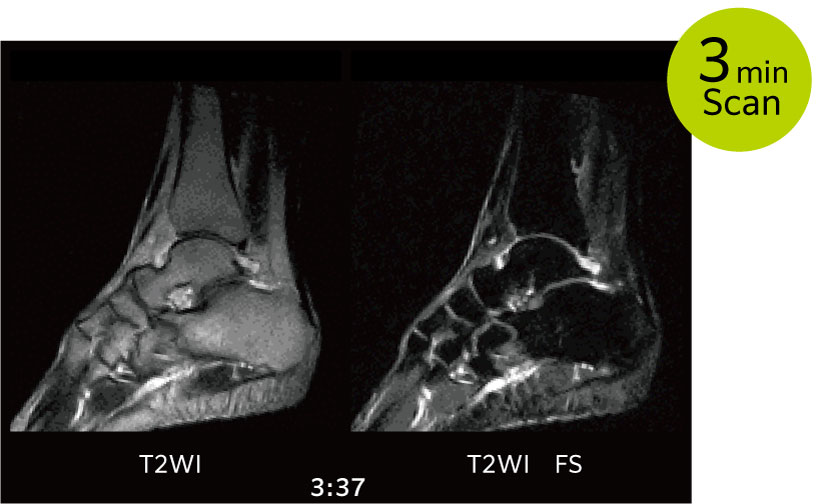

IP-RAPID is a fast scanning technology that reduces scan time while maintaining image quality undersampling and iterative reconstruction. It can be used in conjunction with various functions and over a wide range of anatomical regions.

IP-RAPID offers higher resolution images without increasing scan time.

IP-RAPID can be combined with various pulse sequences such as FatSep that can offer multiple contrast images with one acquisition.